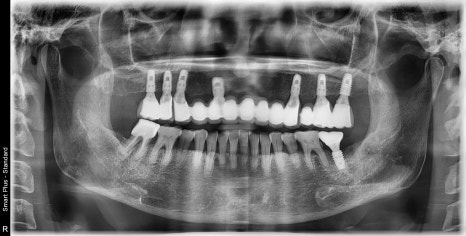

초진 엑스레이 사진입니다.

상악은 무치악 상태이고

하악은 맨 끝 어금니 하나가 치주 질환이 많이 진행되었습니다.

상악의 상악동(=부비동)이라고 하는 공간 때문에

치조골의 높이가 부족해 보입니다.

오른쪽의 최종 보철물이 체결된 상태의 엑스레이 사진입니다.

앞니쪽의 뼈는 너무 종잇장처럼 얇아있기 때문에

최대한 골의 양이 허용되는 범위내에서 심고

작은어금니에서 지지를 같이 받는 구조로 설계를 하였습니다.